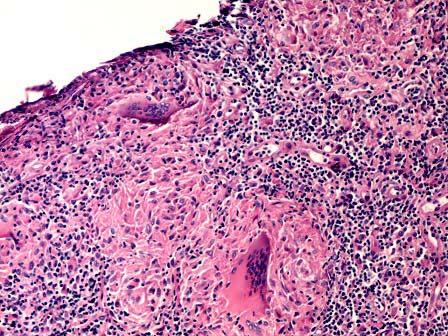

问题 女性,40岁,左侧乳房无痛性肿块半年余。大体见窦道及干酪样坏死区。显微镜下见干酪样坏死、类上皮细胞、郎罕氏巨细胞形成的肉芽肿(如图)。诊断为 ( )

选项 A.脂肪坏死 B.乳汁潴留性囊肿 C.乳腺导管扩张症 D.结核 E.异物肉芽肿

答案 D